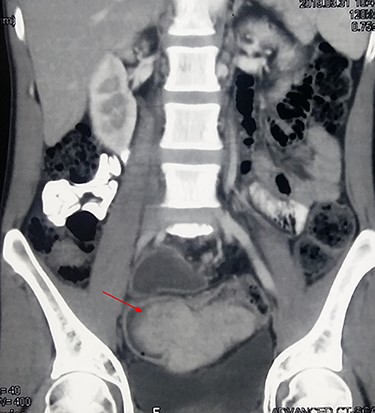

A 35-year-young gentleman presented to emergency department with 4-months history of blood mixed stool and fever (low-grade) for 1 week duration. He also complained of significant weight loss, anorexia and easy fatigability. On general physical examination, pallor was present, with localized tenderness in the left iliac fossa. His vitals were stable. Digital rectal examination revealed blood mixed stool without any intraluminal growth. The laboratory investigation revealed anemia (hemoglobin—7.6 g/dl), leucocytosis (total counts—14 600 cells/mm3) and normal liver and renal function tests. The serum carcinoembryonic antigen was within normal range. The contrast computed tomography (CT) abdomen and pelvis was done, which showed a large (8 × 5 cm), well-defined, homogenously enhancing intraluminal soft tissue lesion in the sigmoid colon, with few pericolic lymph nodes (Fig. 1). There were no features of intrabdominal metastases.

Contrast CT showing a large, enhancing, intraluminal soft tissue tumor (arrow) in the sigmoid colon.

On contrast CT, the lesion does not have any specific features suggestive of IMFT. It can appear as ill-defined, nonencapsulated, protruding or infiltrative mass [8]. In the present case, it was large, intraluminal, well-defined, homogenously enhancing tumor mimicking lymphoma or gastrointestinal stromal tumor. The tumor in no way looked like a colonic carcinoma on imaging. On colonoscopy, the tumor appears as intraluminal soft tissue mass, with surface ulceration and intact mucosa. The biopsy usually reveals chronic inflammation [6]. In our patient, the colonoscopy was not done, as the tumor was bleeding with anemia, with probable localized perforation. Furthermore, the report would have not changed the management as the patient was planned for emergency surgery.